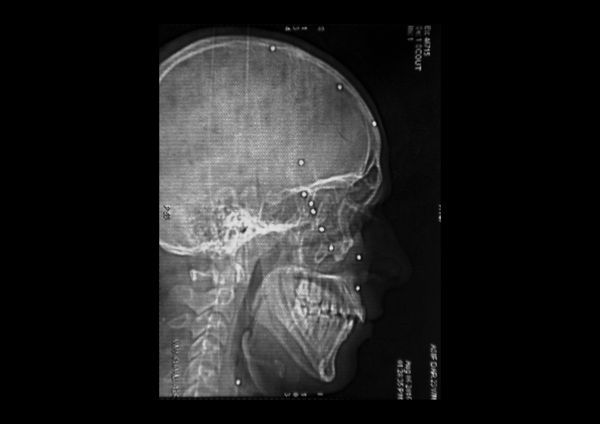

A visual investigation about the disastrous effects of the pellet guns used by the Indian army and the police forces in the Valley of Kashmir, India.

According to a UN report released in 2018, the new weapon is responsible for blinding around 1000 people and killing dozens.

Carrying dozens of pellets in their bodies, victims face unknown long term health consequences.